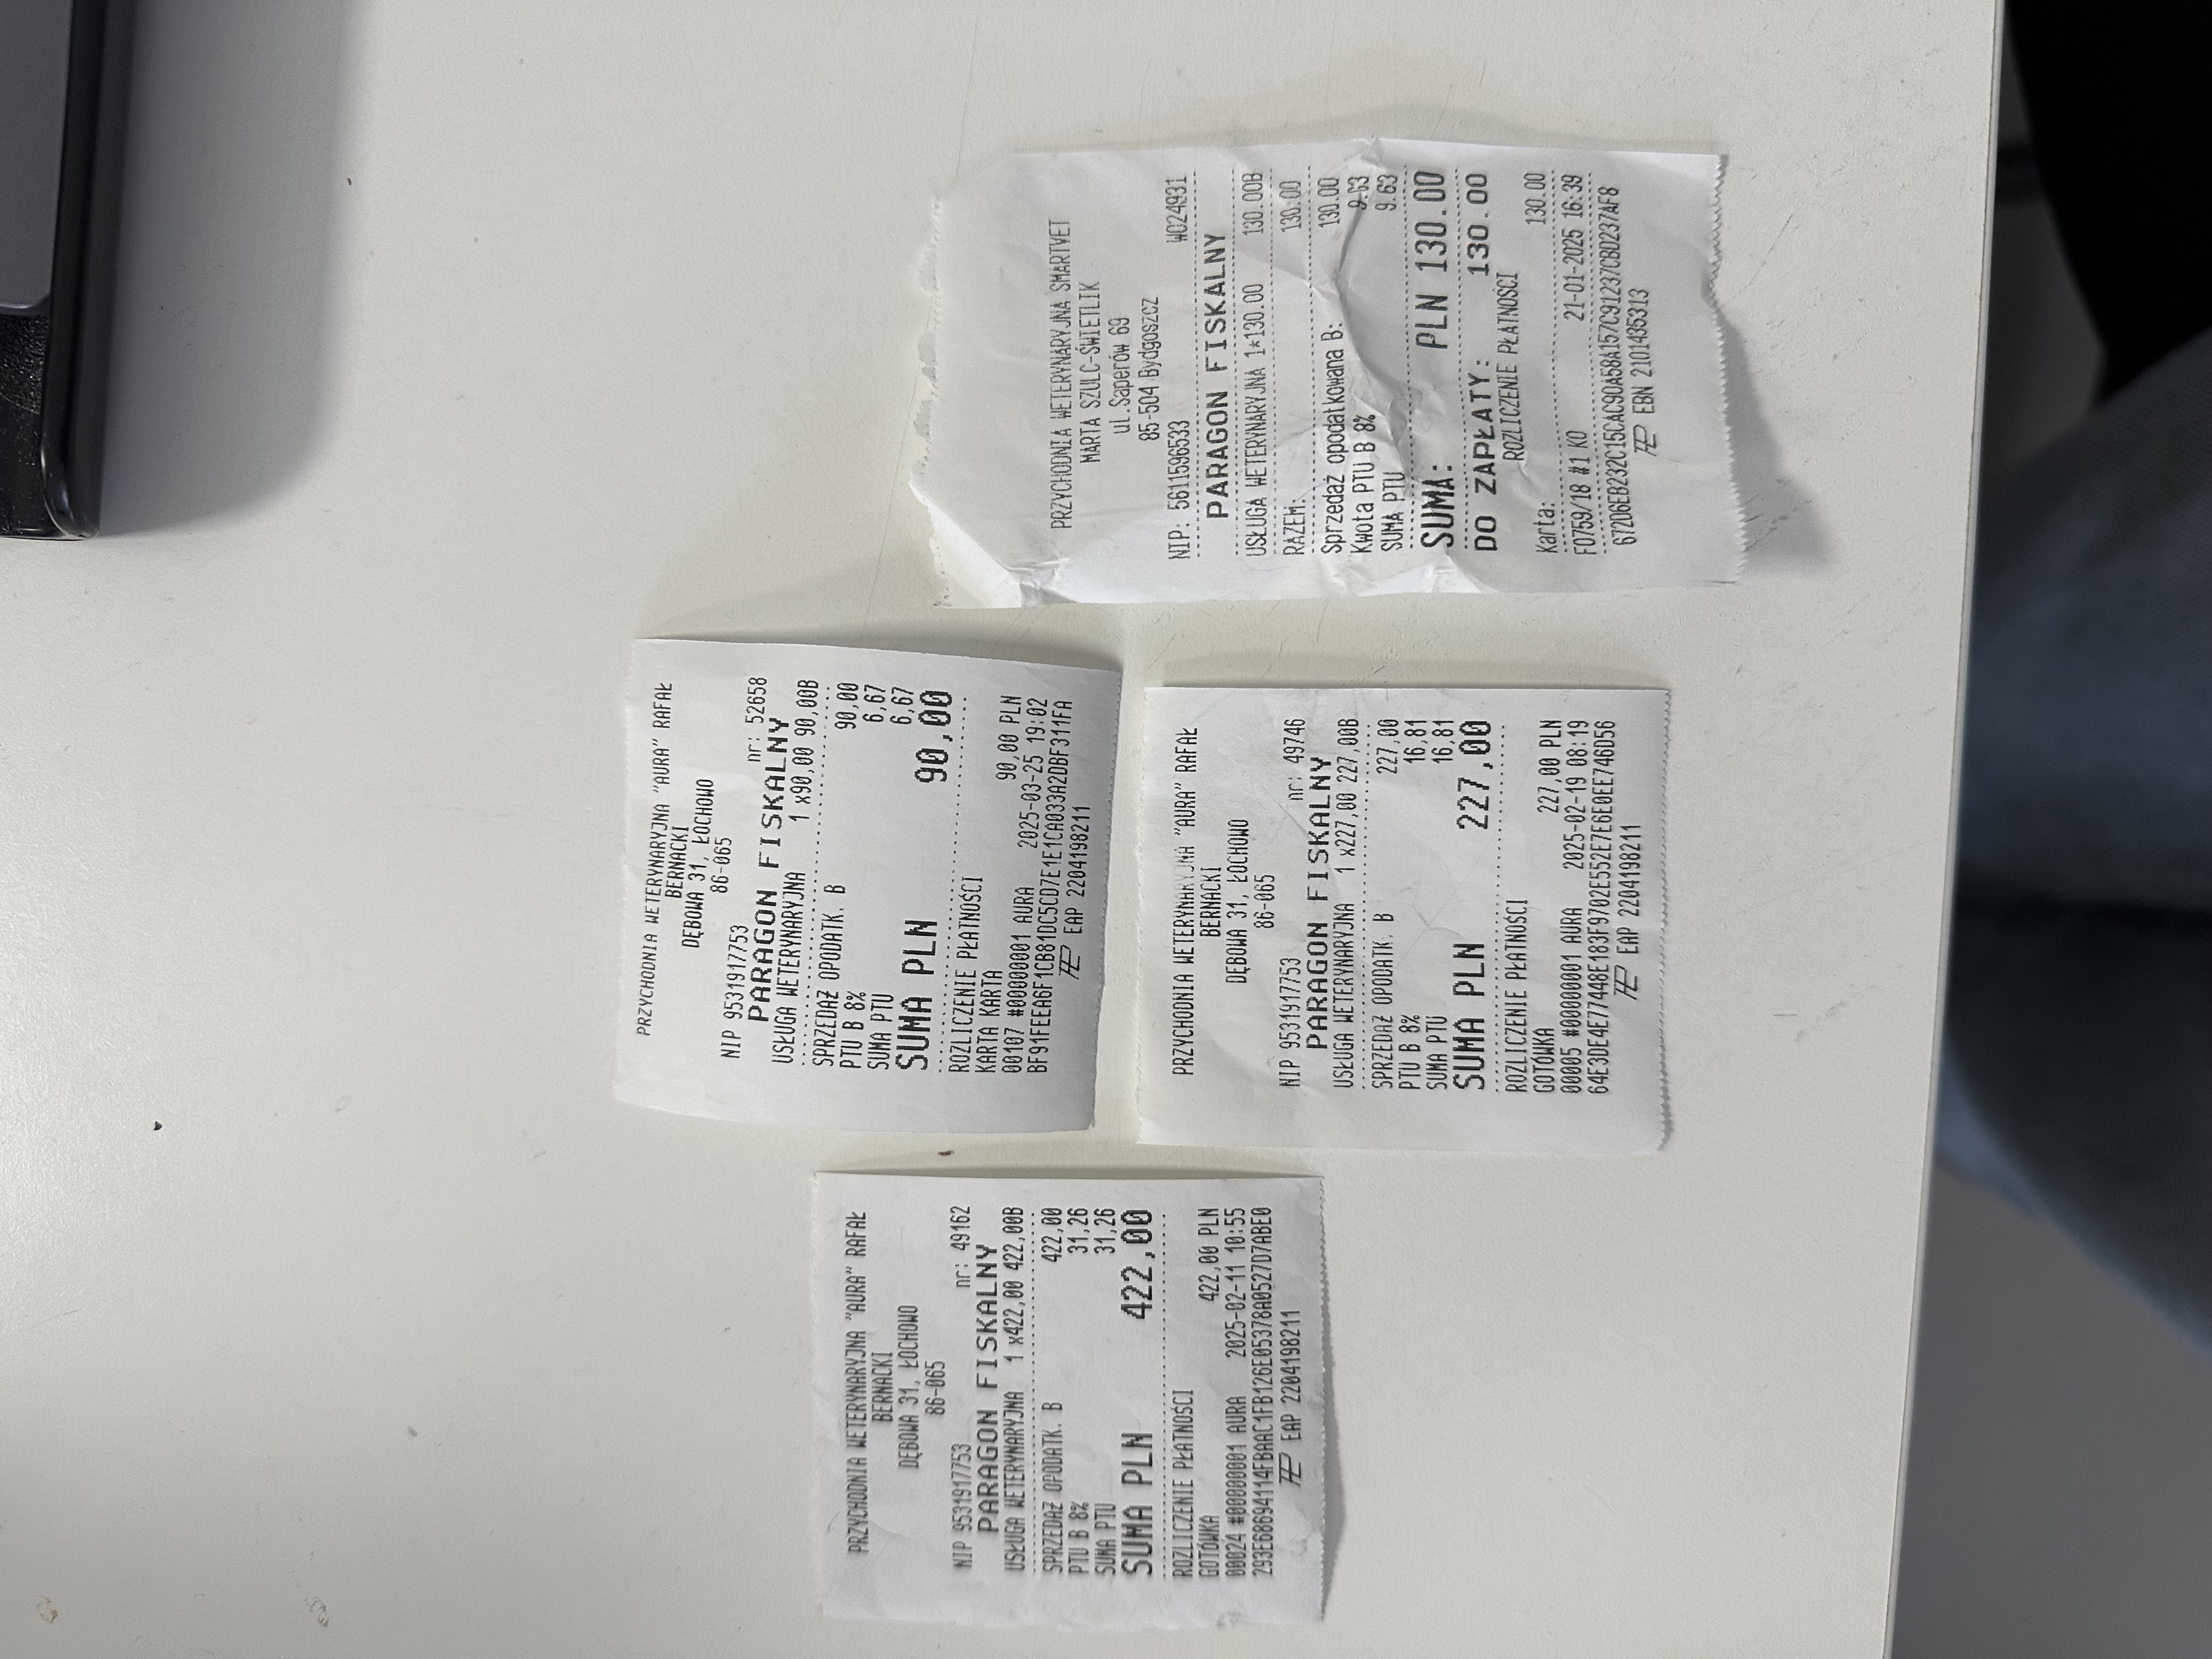

Pierwsza wizyta u weterynarza wykazała możliwe problemy ortopedyczne – Fudżi wykazywał silny stres, miał napięty grzbiet, a próba wyprostowania jego stawów biodrowych wywoływała agresję, co mogło świadczyć o bólu. Wstępnie podano mu leki przeciwbólowe (Loxicom, Rheumocam) i zalecono dalszą diagnostykę.

Kolejna konsultacja miała miejsce w innej klinice, gdzie lekarze nadal podejrzewali problemy ortopedyczne, dlatego przeszedł szczegółowe badania, w tym RTG kręgosłupa i bioder i konsultacje specjalistyczną. Wdrożono leczenie Gabapentyną oraz Metacamem, aby zmniejszyć ból i uspokoić kota. Zalecono dalszą obserwację oraz ewentualne kolejne badania, jeśli objawy nie ustąpią.

Badania ortopedyczne oraz biochemia wraz z morfologią nie wykazały poważnych zmian (lekarza poinformował, aby nie decydować się na badanie TK/MRI, ponieważ podłoże problemu leży gdzieś indziej; a z USG się wstrzymać).

Pojawiło się podejrzenie Feline Hyperesthesia Syndrome (FHS) – zaburzenia neurologicznego, które może powodować nadwrażliwość skóry, niekontrolowane reakcje bólowe oraz zmiany w zachowaniu, a także zostało przeprowadzone badanie kliniczne i nie wykluczono problemów dermatologicznych w związku z agresywnym wydrapywaniem futerka (alergia, pasożyty). Zalecono obserwację i sprawdzenie reakcji na leki sterydowe.

Lekarz wprowadził leczenie objawowe, aby sprawdzić, czy Fudżi dobrze na nie zareaguje: Amitryptylina – lek przeciwdepresyjny i przeciwbólowy, stosowany przy zaburzeniach Pnrednicorton (steryd) – silny lek przeciwzapalny, mający zmniejszyć stan zapalny i świąd.

Fudżi nadal wymaga diagnostyki oraz możliwego rozszerzenia leczenia. Jeśli obecna terapia sterydowa przyniesie poprawę, konieczne będzie wykonanie dalszych badań w kierunku alergii/atopii i nie potwierdzi się występowanie zespołu FHS.